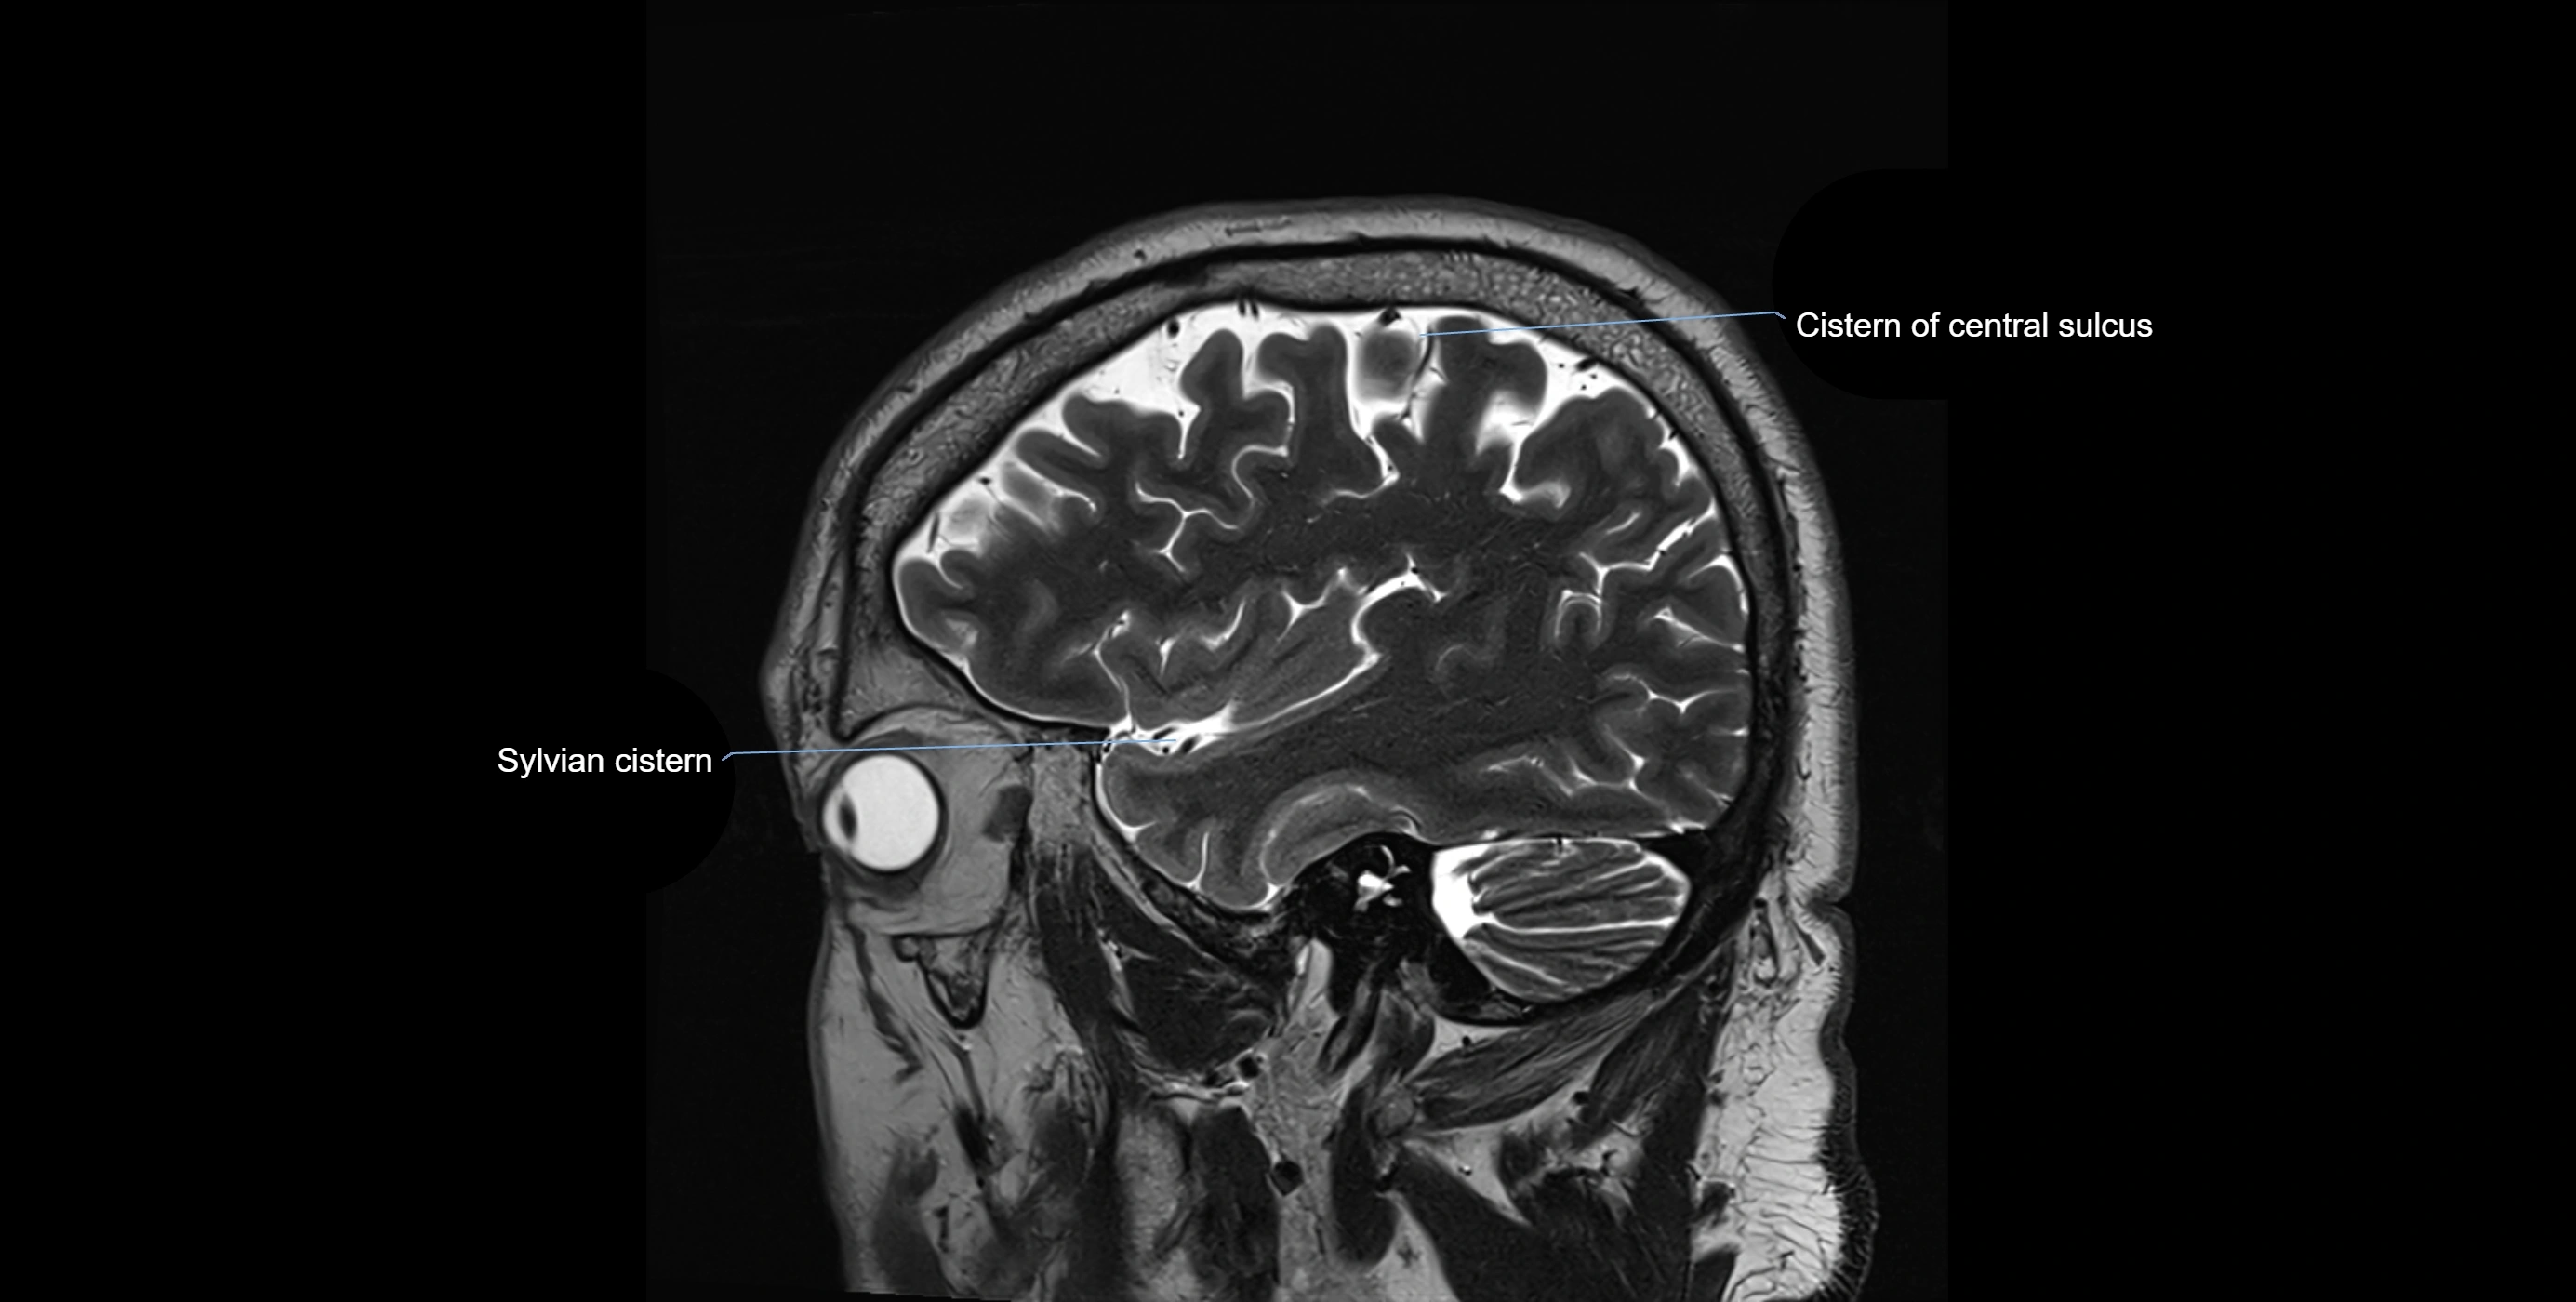

MRI images

image